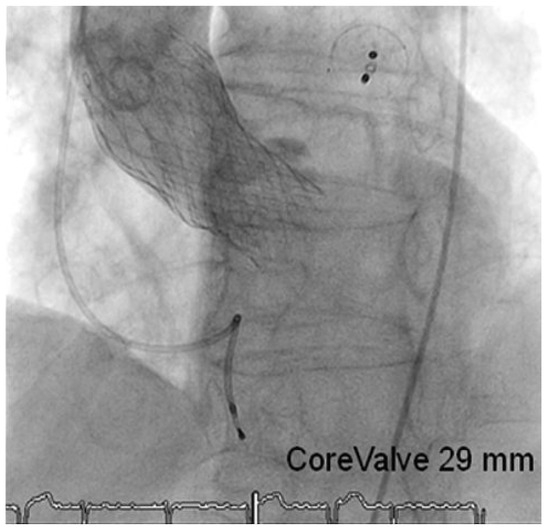

Case Report

Comprehensive “One Stop-Shop” Percutaneous Cardiac Intervention

by Thomas Pilgrim, Peter Wenaweser, Stephan Windecker and Bernhard Meier

Cardiovasc. Med. 2010, 13(5), 171; https://doi.org/10.4414/cvm.2010.01497 - 26 May 2010

A 78-year-old male retired mathematician with severe aortic stenosis, persistant atrial fibrillation, reluctance to accept oral anticoagulation, and with suspected coronary artery disease was referred for further management [...] Full article

Show Figures

Figure 1